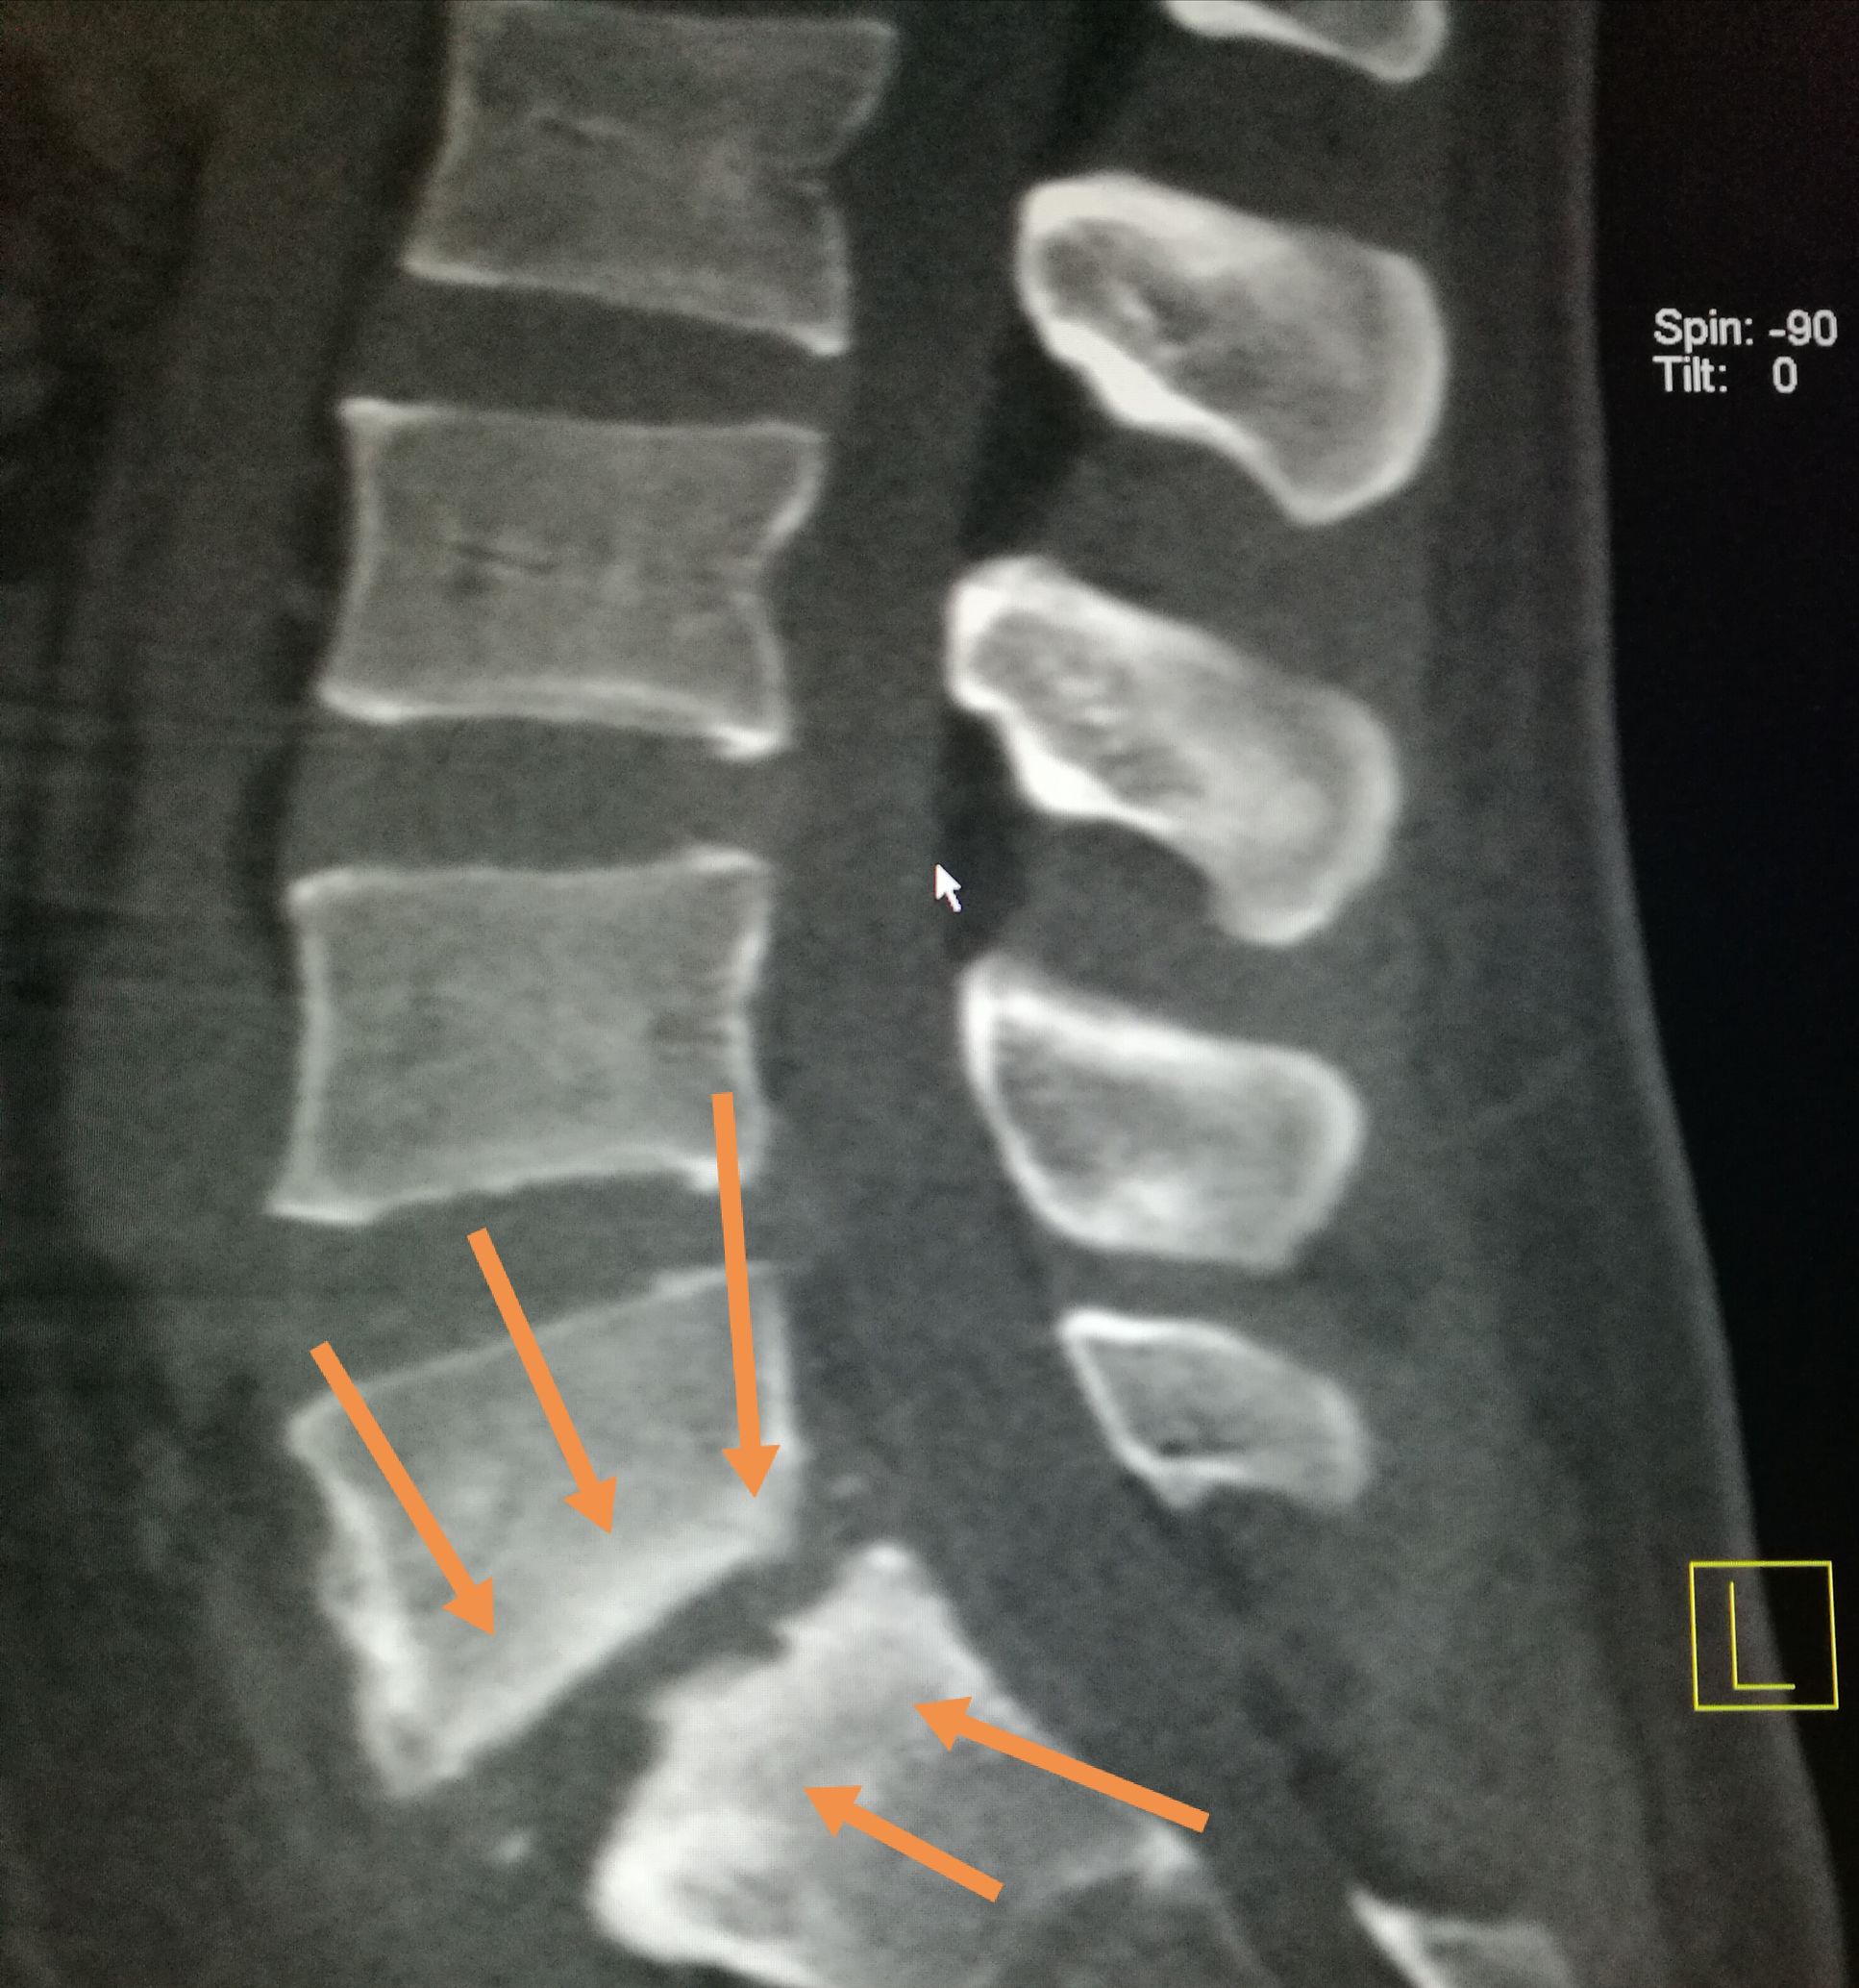

吃羊肉腰胀疼是怎么了,经常吃牛羊肉身体有啥变化 ​​​患者,男,22岁,以腰疼数月前来我处就诊,CT扫描可见第五腰椎下缘,骶椎上缘骨质破坏,骨密度增高,椎间隙未见明显狭窄,椎体旁未见软组织肿胀,未见异常包块,随后追问病史,主诉在*疆新**生活两年,后腰疼,在省防疫站查出来是布鲁氏杆菌感染,今来我处复查。